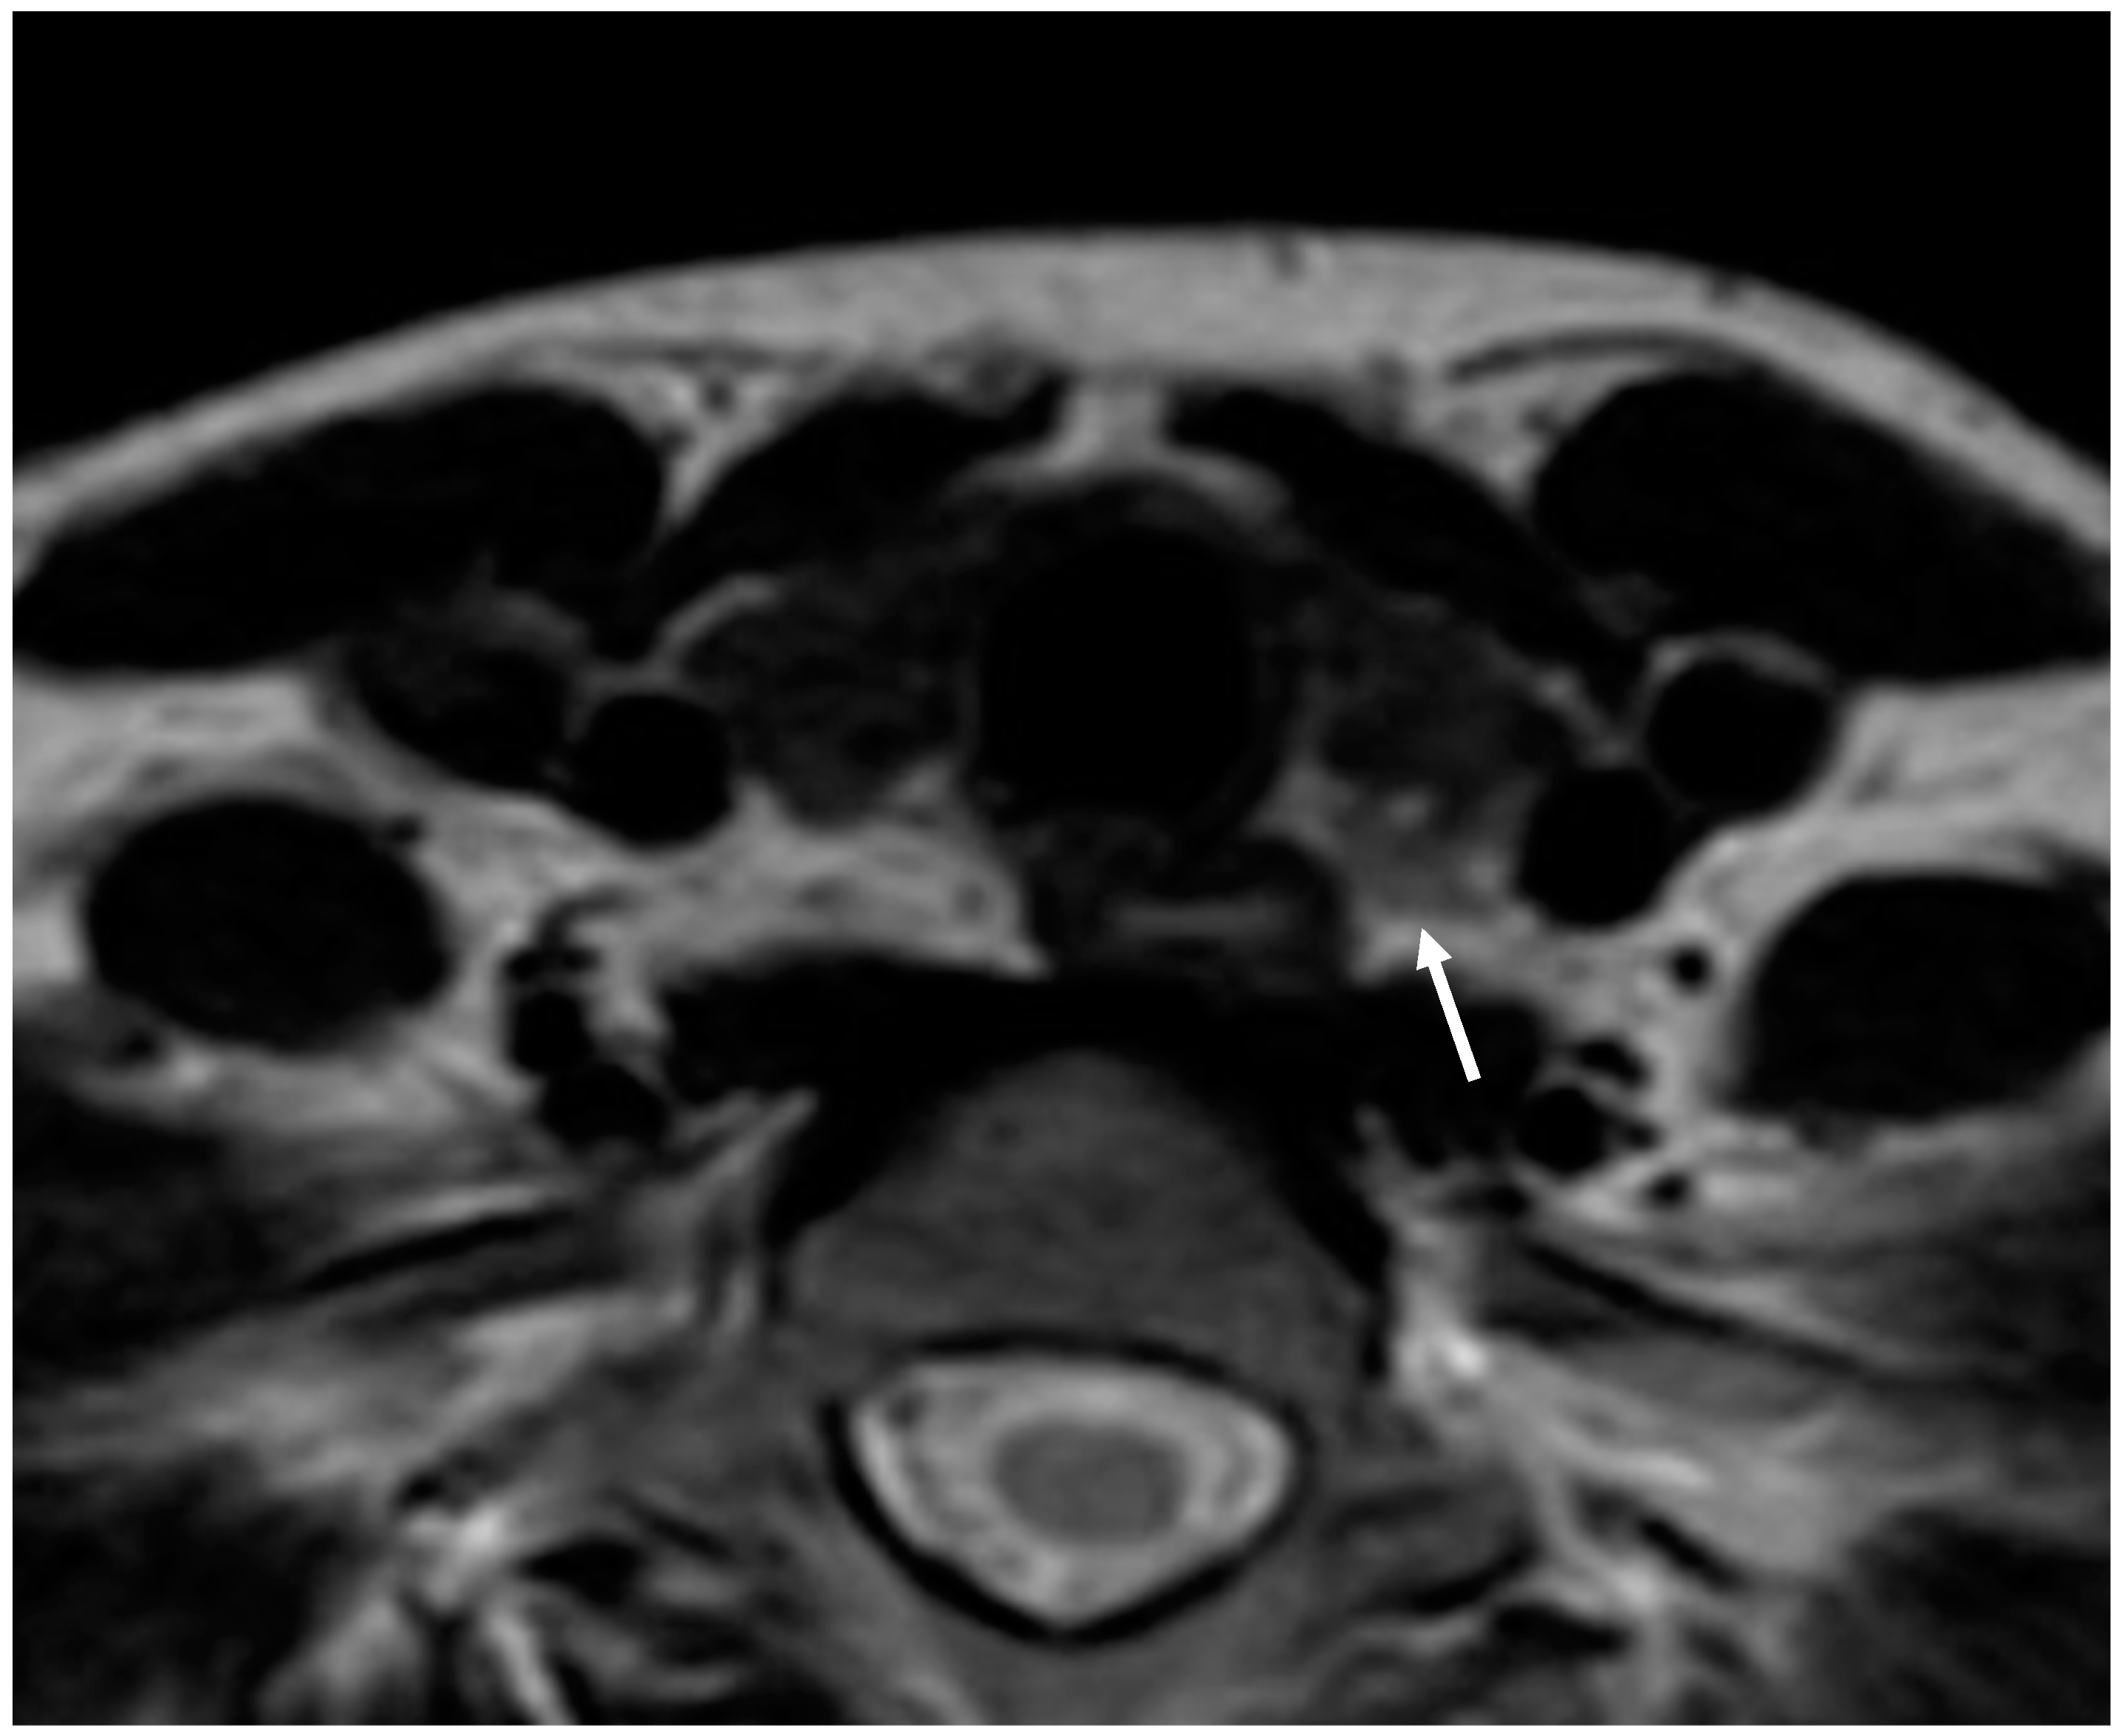

Parathyroid adenoma is usually seen as a mass with a uniform intermediate-to-high signal on T2-weighted sequences and low signal intensity on T1-weighted sequences. The routine use of MRI contrast agents is not firmly established (Figure 4).

Figure 4.

Parathyroid adenoma. Axial T2-weighted image shows a small iso-hyperintense mass behind the left thyroid lobe (arrow).

MRI has a variable accuracy for detecting hyperfunctioning parathyroid tissue, with reported sensitivities ranging from 39 and 94%, and specificity of 82–85% [29]. The combination of MRI and 99mTc-sestamibi scintigraphy increases sensitivity to 94% [24]. Furthermore, MRI offers advantages over CT, such as there being no ionizing radiation or the need for iodinated contrast media.